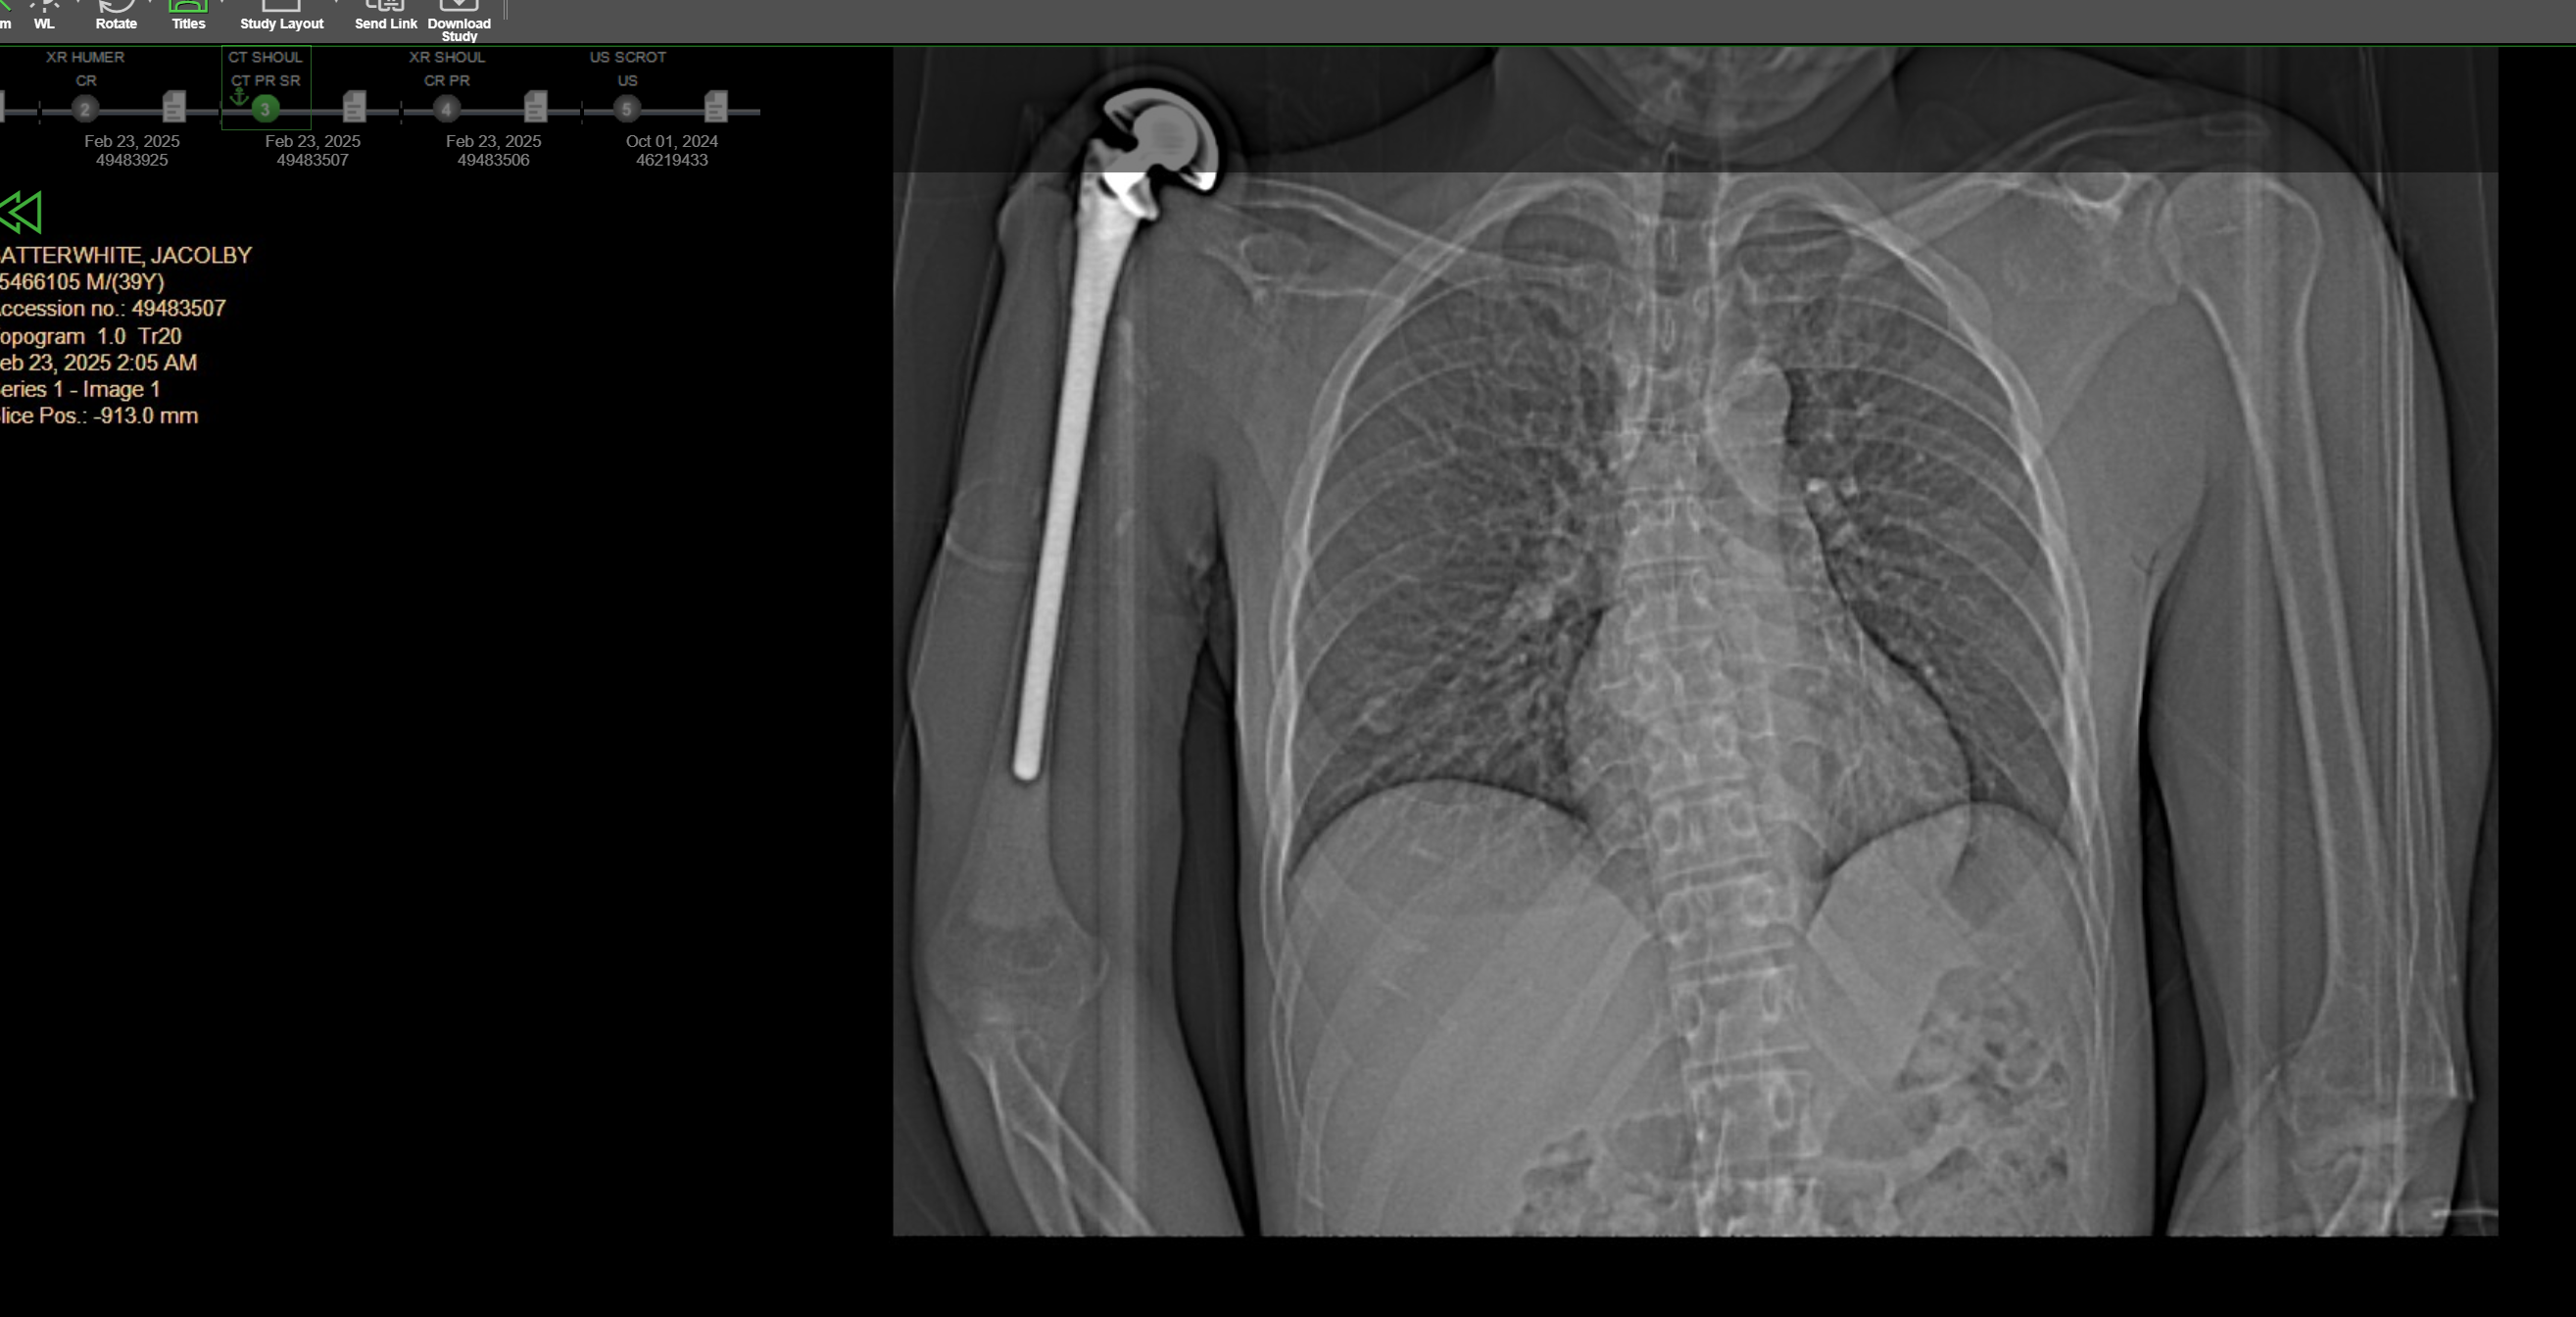

A two-time cancer survivor, Jacolby has lived with a prosthetic, cemented to the bone in his right arm and shoulder since childhood. Despite limited mobility, he has built an extraordinary career as a visionary artist and filmmaker, with exhibitions in major galleries and museums worldwide.

Over the past year, Jacolby has undergone extensive bouts of antibiotics and care to manage his symptoms. But recently, he developed a catastrophic, life-threatening infection in his prosthetic– which has now ruptured into a grapefruit-sized open wound on his shoulder, completely exposing the bone below his skin. The infection has begun to impact other organs, and urgent surgery is now required to save his life.

- Complete removal of the infected prosthetic and surrounding muscle -The prosthetic will have to be chiseled off of what's left of Jacolby's original humerus, as they're cemented together